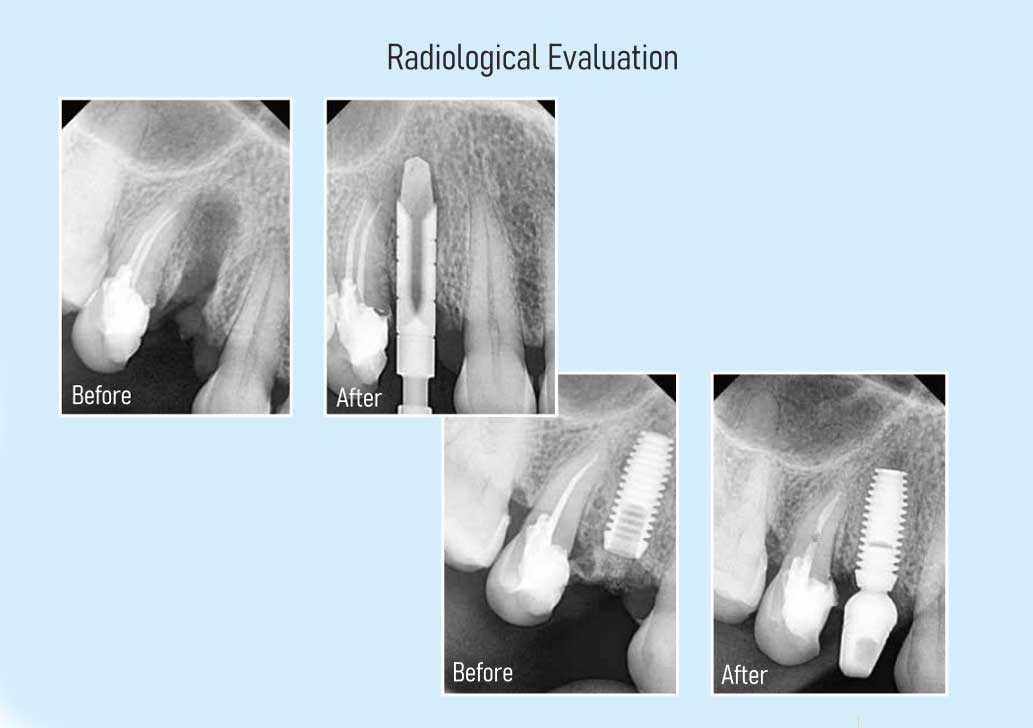

Two Stage Implants

The procedure is carried out in two stages spread over a mini- mum interval of 3 months. The first stage involves the placement of the implants and requires one to two sessions. The second stage involves the fabrication of the crowns (teeth). This is an obsolete technology and only used in those few cases where single stage implants are clinically not possible.

Single Stage Implants

The latest in dental implant technology, this involves comple- tion of the entire procedure, right from extractions, implant placements and fabrica- tion of the crowns (teeth) in one stage of approximately two weeks. This system can be used for almost all types and categories of cases.